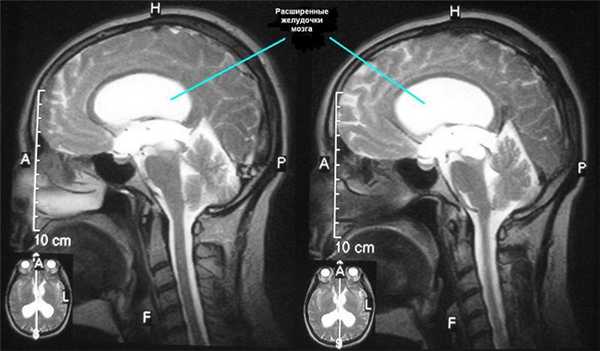

У детей с врожденной гидроцефалией повышение внутричерепного давления долго компенсируется увеличением объема полости мозгового черепа за счет расхождения черепных швов. При этом происходит расширение мозговых желудочков. Различают следующие варианты врожденной гидроцефалии.

Клинические проявления гидроцефалии различны. В грудном возрасте может возникать истончение мозговой коры, что выражается такими симптомами, как вялость, пассивность, безразличие, срыгивание, отставание в физическом и психическом развитии. Расхождение костей мозгового черепа и увеличение его размеров может быть заметным уже при рождении или, чаще, становится очевидным к концу 1-2-го месяца, когда происходит интенсивный рост головы. Окружность головы иногда достигает 80-100 см (в норме окружность головы новорожденного на 2 см больше окружности груди). При этом выявляются расширение заднего и особенно переднего родничков, их незарастание и напряжение мягких тканей над ними. Вены покровных тканей головы инъецированы и хорошо видны, особенно во время крика, через истонченную полупрозрачную кожу. Кости черепа также истончены. Обращают внимание редкий волосяной покров, непропорционально большой и нависший над лицевым черепом лоб - симптом балкона. Возможна деформация глазниц. В ряде случаев наблюдается экзофтальм. При перкуссии свода черепа баллотирование его костей сопровождается своеобразным резонирующим звуком «треснувшего горшка» - симптом Маккьюна.

- КТ и МРТ, позволяющие точно определить степень гидроцефалии и выявить наличие церебральных мальформаций;